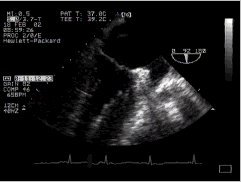

3. RVOT, MPA

4. thumbnail ME SAX Longitudinal right ventricular outflow CLICK FOR VIDEO: right ventricular outflow (longitudinal)

The right ventricular outflow tract is well shown here, and can be followed on the right up to the main pulmonary artery. Closer to the probe is the aortic valve, just beginning to appear as the left ventricular outflow tract leads into it, and closer still (more posterior) the left atrium.